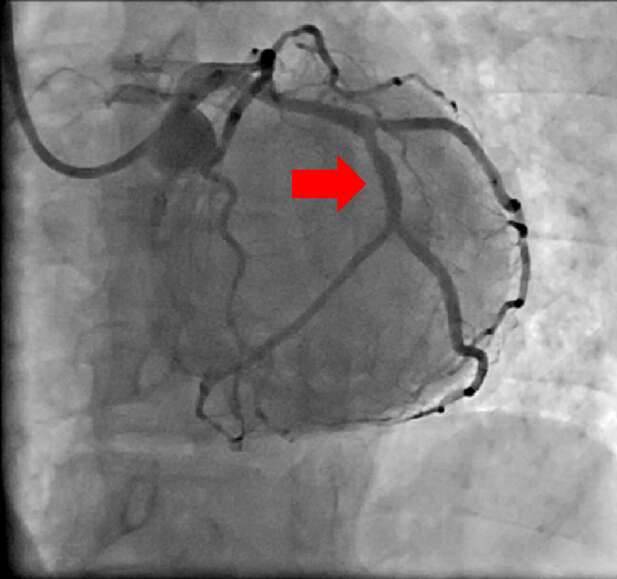

【治療例3:狭心症ステント拡張術】

治療前

赤矢印の冠動脈が狭窄している

治療後

狭窄していた冠動脈にステントを留置し、血流が元に戻っている